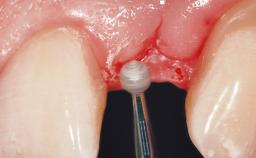

A 30-year-old female patient was referred to the office for the treatment of tooth 11. Her chief concern at the initial visit was to inquire, “Why is my tooth pink?” Upon clinical examination, it was determined that tooth 11 had a previous history of trauma and that the clinical crown had become noticeably pink in color as a result of internal resorption. This diagnosis was confirmed radiographically, indicating a large radiolucency involving the central and distal portions of the clinical crown. It was determined that restoration of this tooth was not possible, and that extraction was indicated. The presence of a mid-line diastema, which the patient wanted to reproduce, directed the treatment plan for tooth replacement utilizing a dental implant.

Placement Protocol Immediate implant placement

Tooth Site Maxillary incisor or canine

Socket Morphology Single-root socket

Socket Integrity Sufficient, with intact bone walls

Bone Volume Sufficient, with intact walls